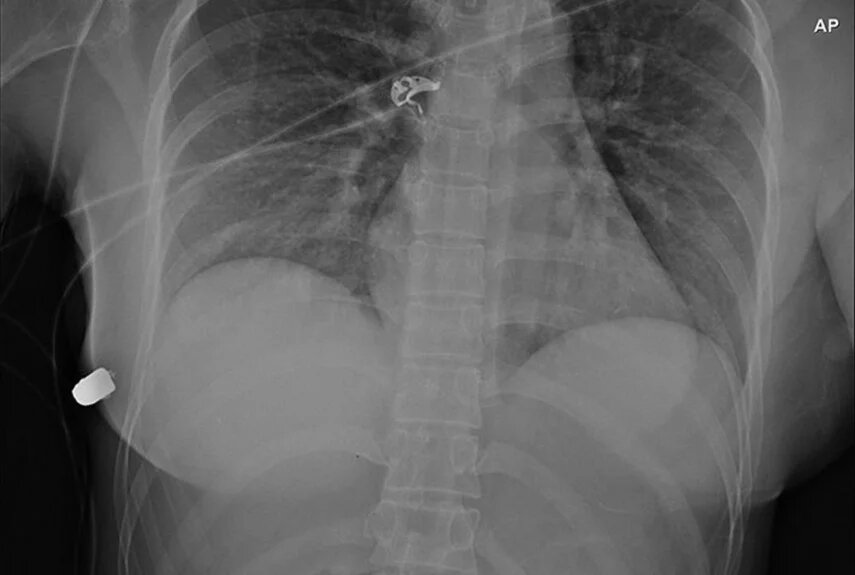

Рентген органов подтвердил, что инородный элемент — пуля, пробившая ребро. Компьютерная томография показала ушиб легкого, а также следы осколков. Это значило, что пуля повредила сразу два грудных импланта.

Фото: ScienceAlert